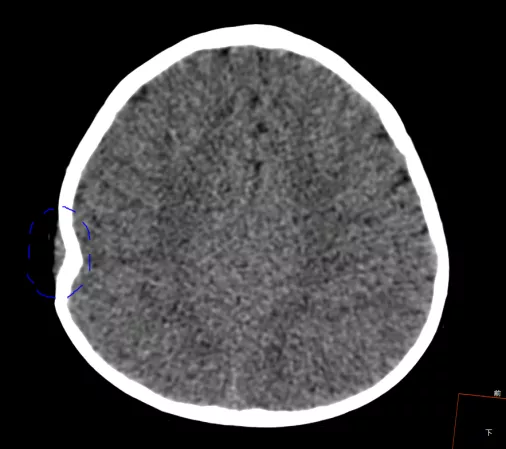

這名11個月的寶寶被撞後,當場昏迷,醫院檢查發現其顱骨骨折(圖中藍色區域)、顱內大面積出血,傷勢已經危及生命。

所幸經過神經外科醫生全力搶救,孩子的生命得以保住。